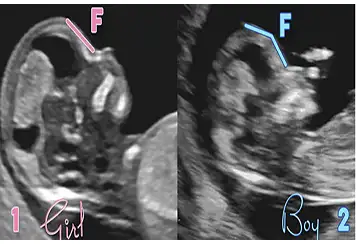

Bebeğimin cinsiyeti

• 20220913_122703_001.webp